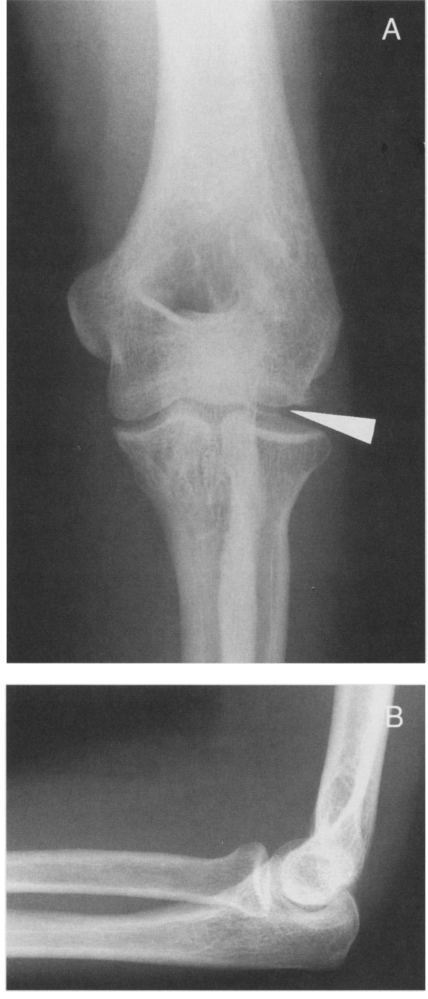

Женщина, 47 лет. Получила травму локтевого сустава в результате падения с высоты собственного роста, около 3 месяцев назад. На момент осмотра контуры локтевого сустава сглажены, беспокоит боль как при движениях, так и в покое. Объем движений резко ограничен и находится в пределах 40 градусов.<br /><br />Рентгенограммы:<br /><br />

<br />Только перелом головки (головчатого возвышения, capitulum) плечевой кости 1 типа.<br /><br />Hahn лечил 63 летнюю женщину с травмой локтевого сустава 3-х летней давности и впервые в мировой литературе описал эту травму в 1853 году. К сожалению, результат лечения был неудовлетворительный.<br /><br />В последующие годы была предложена классификация переломов головки плечевой кости, в которой было выделено 4 типа:<br /><br />1 тип (Hahn-Steinthal type) представляет собой, т. наз. "полный перелом", при котором головка типично смещается кпереди и вверх. Плоскость излома лежит во фронтальной плоскости, а костный фрагмент по сути представляет свободное тело в полости сустава.<br /><br />

<br /><br />Через 3 месяца после перелома при традиционных рентгенограммах диагностика трудна. На КТ-сканах головка лучевой кости, как бы вклинивалась в зону перелома. Была выполнена открытая репозиция и фиксация перелома с помощью 2-х винтов Герберта. <br /><br />К сожалению, доктора, который пропустил при первом обращении пациентки этот перелом, сейчас ждет суд